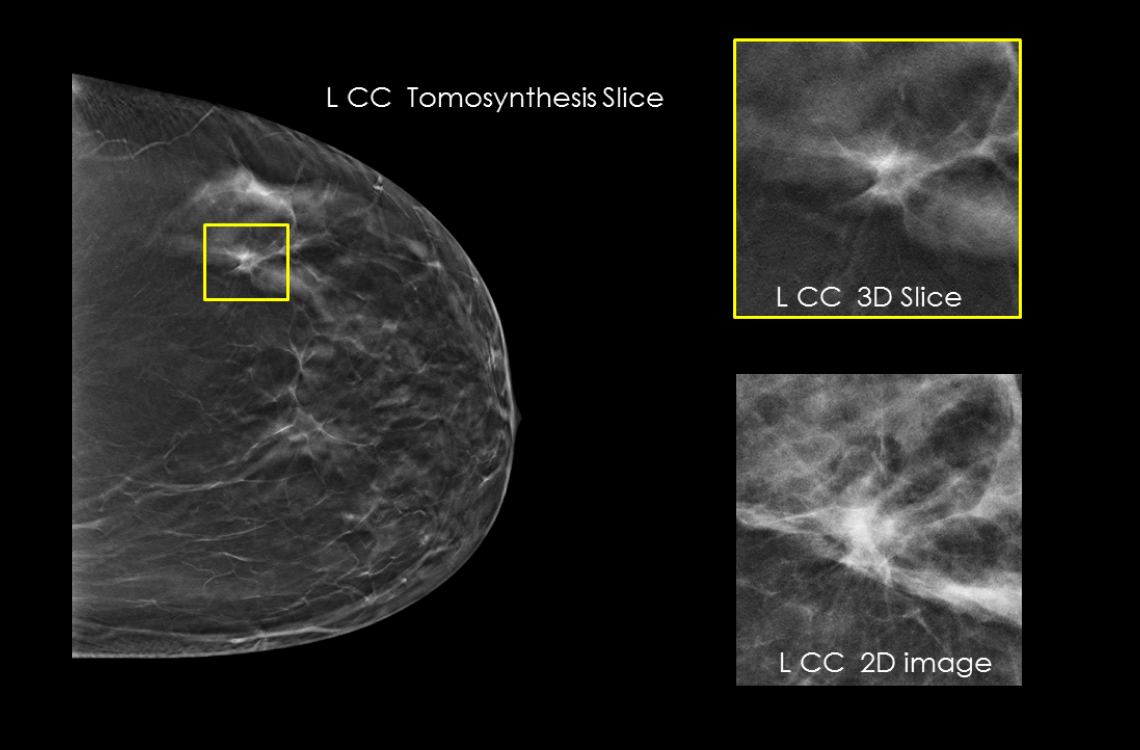

- Proven to detect 20%-65% more invasive breast cancers compared to 2D alone, an average increase of 41%.1

- Proven to reduce callbacks by up to 40% compared to 2D alone.2-3

- FDA approved as superior for women with dense breasts compared to 2D alone.2,4

Hologic has further advanced breast cancer screening by producing 2D images from breast tomosynthesis data using C View software, resulting in a Low Dose Genius 3D Mammography exam with superior clinical performance compared with 2D alone.4

This Low Dose Genius 3D Mammography exam is performed in a rapid 3.7 second scan time for greater patient comfort and low patient dose, due to the elimination of 2D X ray exposures. The synthetic 2D images and 3D slices are reviewed together to make clinical decisions or diagnoses part of the Genius 3D Mammography screening exam.